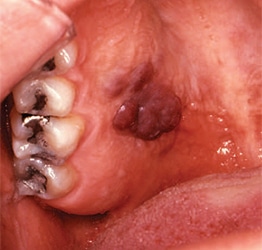

- Kaposi’s sarcoma appears as a macular or nodular lesion. It may or may not be ulcerated. These lesions can be red or even purple, and older lesions are darker (Figure 1).